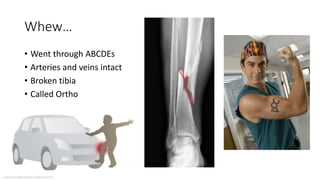

Whew…

• Went through ABCDEs

• Arteries and veins intact

• Broken tibia

• Called Ortho